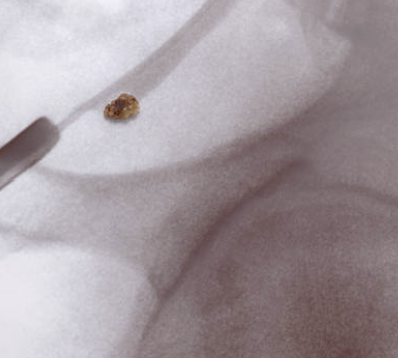

요로 결석은 요로계(신장, 요관, 방광, 요도)에서 결석이 형성되는 질환으로, 비뇨기계 질환 중 가장 흔한 것 중 하나입니다. 요로 결석은 신장에서 나온 요소들이 모여 결정되어 결석을 형성하고, 이 결석이 요관을 통과하려 할 때 발생하는 통증으로 증상을 나타내며, 요관 통과 과정에서 출혈 등의 합병증이 생길 수 있습니다. 요로 결석은 소변에서 나오는 성분의 양과 질에 따라 발생할 수 있으며, 당뇨병, 고혈압 등의 질환과 관련되어 있습니다.

요로 결석은 비뇨기계에서 나온 성분이 모여 결정을 형성하고 이 결정이 요관에서 움직이면서 통증을 유발하는 질환입니다. 따라서 요로 결석의 대표적인 증상은 다음과 같습니다.

요로 결석의 증상은 결석 크기, 위치, 상태, 개인의 건강 상태 등에 따라 다양하게 나타납니다. 대부분의 경우, 결석이 작으면 자연적으로 배출되거나 약물 치료를 통해 치료됩니다. 하지만, 결석이 크고, 자연 배출이 어려울 경우에는 내시경적 수술이나 초음파 치료 등의 치료가 필요할 수 있습니다. 따라서 요로 결석 증상이 나타날 경우, 적절한 치료를 받기 위해 전문의의 진단과 조언을 받는 것이 중요합니다.